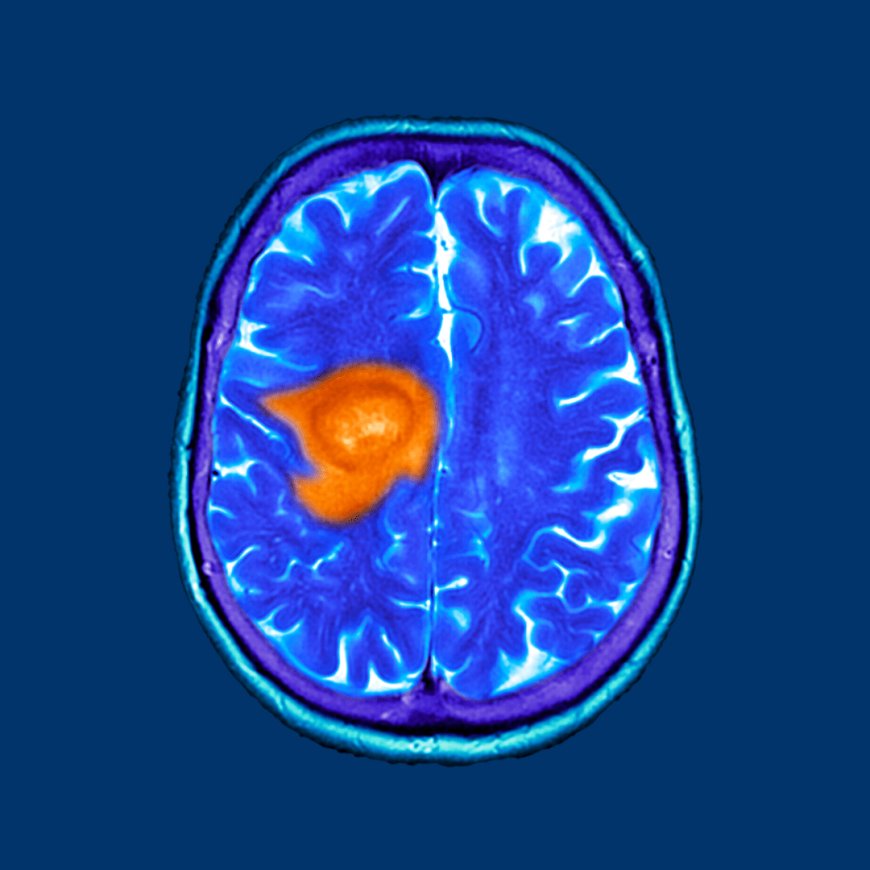

In the ever-evolving field of cancer treatment, complementary therapies are gaining increased attention for their ability to enhance patient outcomes and quality of life. One such emerging therapy is Hyperbaric Oxygen Treatment for Cancer a non-invasive approach that uses pure oxygen in a pressurised chamber to support healing and recovery.

While not a stand-alone cure, this treatment is being recognised for its potential benefits when used alongside conventional cancer therapies like surgery, chemotherapy, and radiation. Lets explore how hyperbaric oxygen therapy (HBOT) works, and why its becoming a supportive option for cancer patients around the world.